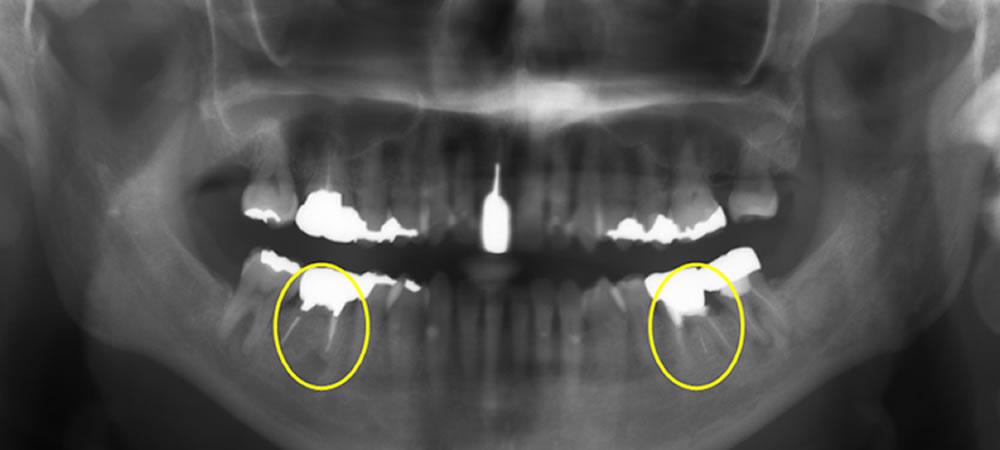

下顎両側の大臼歯を抜歯してインプラントで治療した症例 こちらの患者さまは、右下奥歯が腫れて痛みがあり、食べられないとのことで当院に来院されました。 レントゲン上で右下の6番目の根の先端に大きい影が見られます。また左下も噛 […]